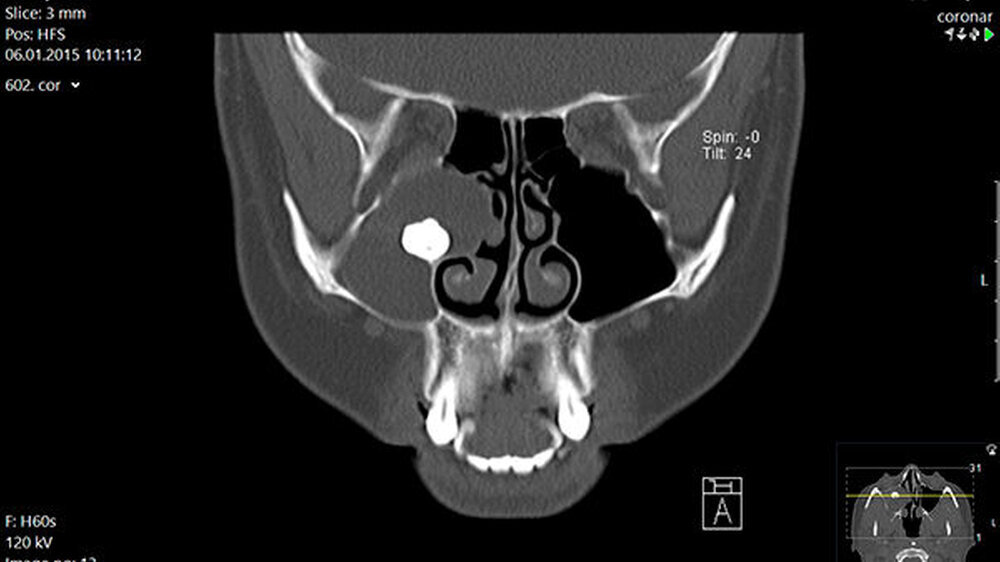

In der regionalen Klinik (Winterberg-Krankenhaus Saarbrücken) wurde zusätzlich eine kontrastmittelunterstützte Computertomografie der Nasennebenhöhlen durchgeführt (Abbildungen 2 und 3), die den Befund bestätigte und präzisierte.

Intraoperativ entleerte sich reichlich eingedicktes Sekret. Die dort ebenfalls veranlasste postoperative Histologie ergab die Kombination einer Kieferhöhlenzyste (respiratorisches Epithel) mit einer odontogenen Zyste (mehrschichtiges nicht keratinisiertes Plattenepithel). Der weitere Verlauf war erfreulicherweise unkompliziert.